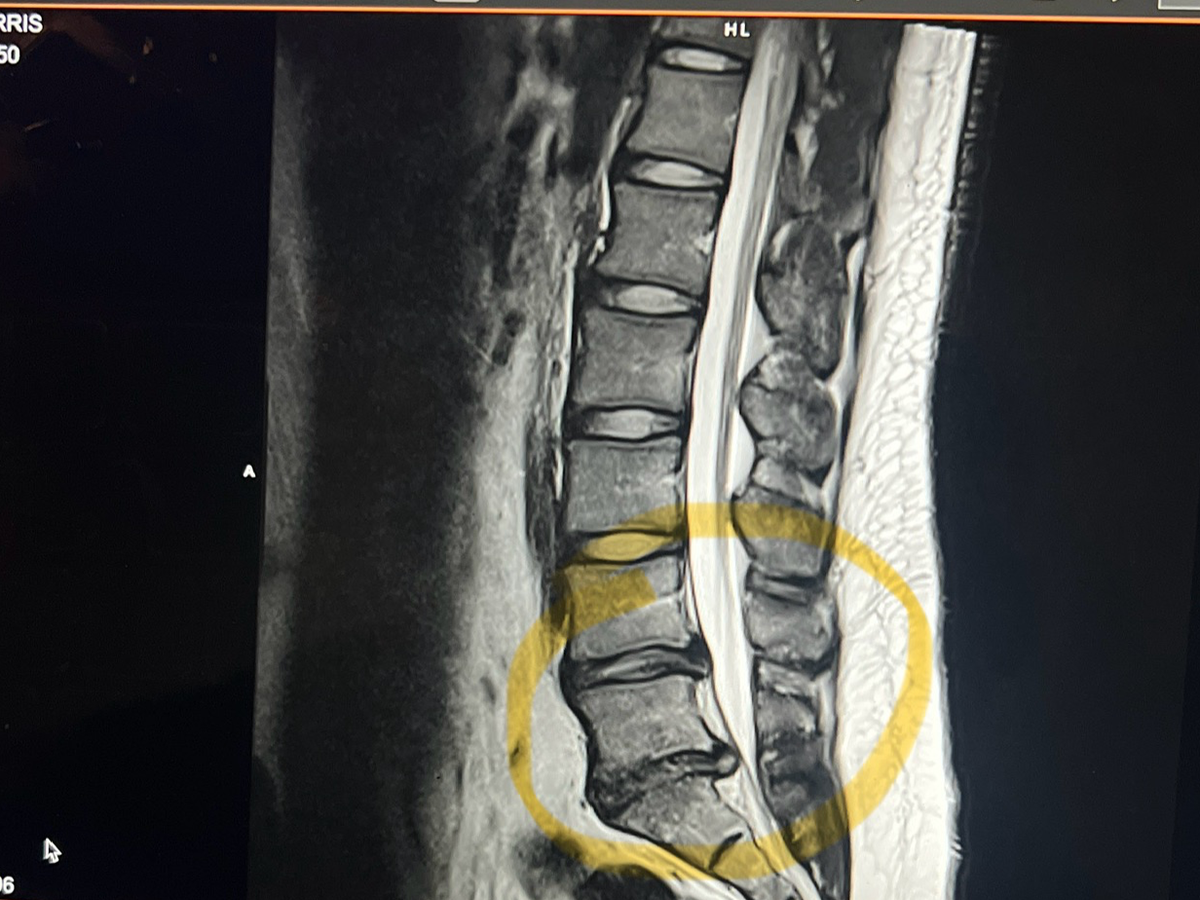

Recently, I was diagnosed with two herniated discs (L4-L5 and L5-S1) that were pressing on my sciatic nerve, causing severe pain and making it impossible to walk, stand, or lift, which are all essential parts of my work. On October 22, 2025, after having tried everything PT, Steroid Injections, Occupational Therapy and more desperately wanting to gain normalcy in my life again, I underwent a micro-discectomy (a minimally invasive surgery to relieve pressure on a spinal nerve caused by a herniated disc) to relieve the pressure on my nerves and begin my road to recovery.